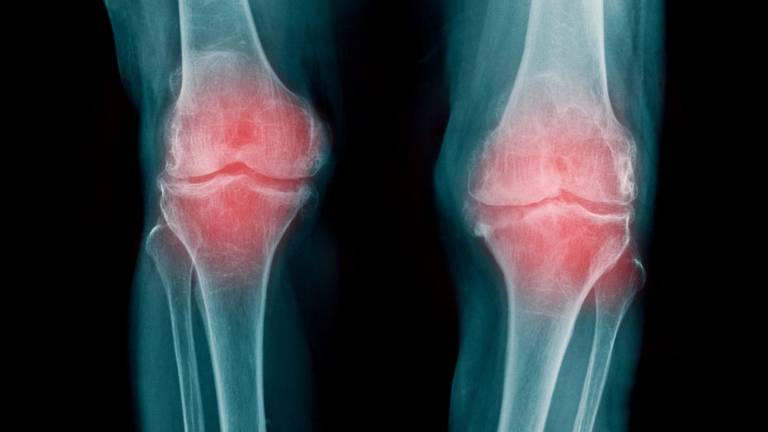

Se trata de una enfermedad crónica y degenerativa que afecta a las articulaciones y conduce a la aparición de dolores y de dificultades que pueden incapacitar seriamente a las personas que la sufren, han recordado los investigadores.

Es además la causa más habitual de dolor y de discapacidad en los adultos y la primera causa de cirugías de reemplazo articular.

En este trabajo, los investigadores provocaron artrosis en la rodilla de ratas jóvenes y luego inyectaron los dos medicamentos experimentales en la articulación de estos animales, y seis semanas después del tratamiento, las ratas que habían recibido esas partículas mostraron una recuperación de su cartílago.

Los investigadores observaron que el cartílago de la rodilla era más grueso, morían menos células y había células que proliferaban activamente, y la enfermedad revirtió hasta una forma "leve" de artrosis (grado I) y no se observaron efectos secundarios negativos.

Por el contrario, las ratas que no habían recibido tratamiento presentaron una artrosis más severa en las rodillas y la enfermedad progresó del grado II al grado IV, el grado máximo de severidad de la enfermedad.